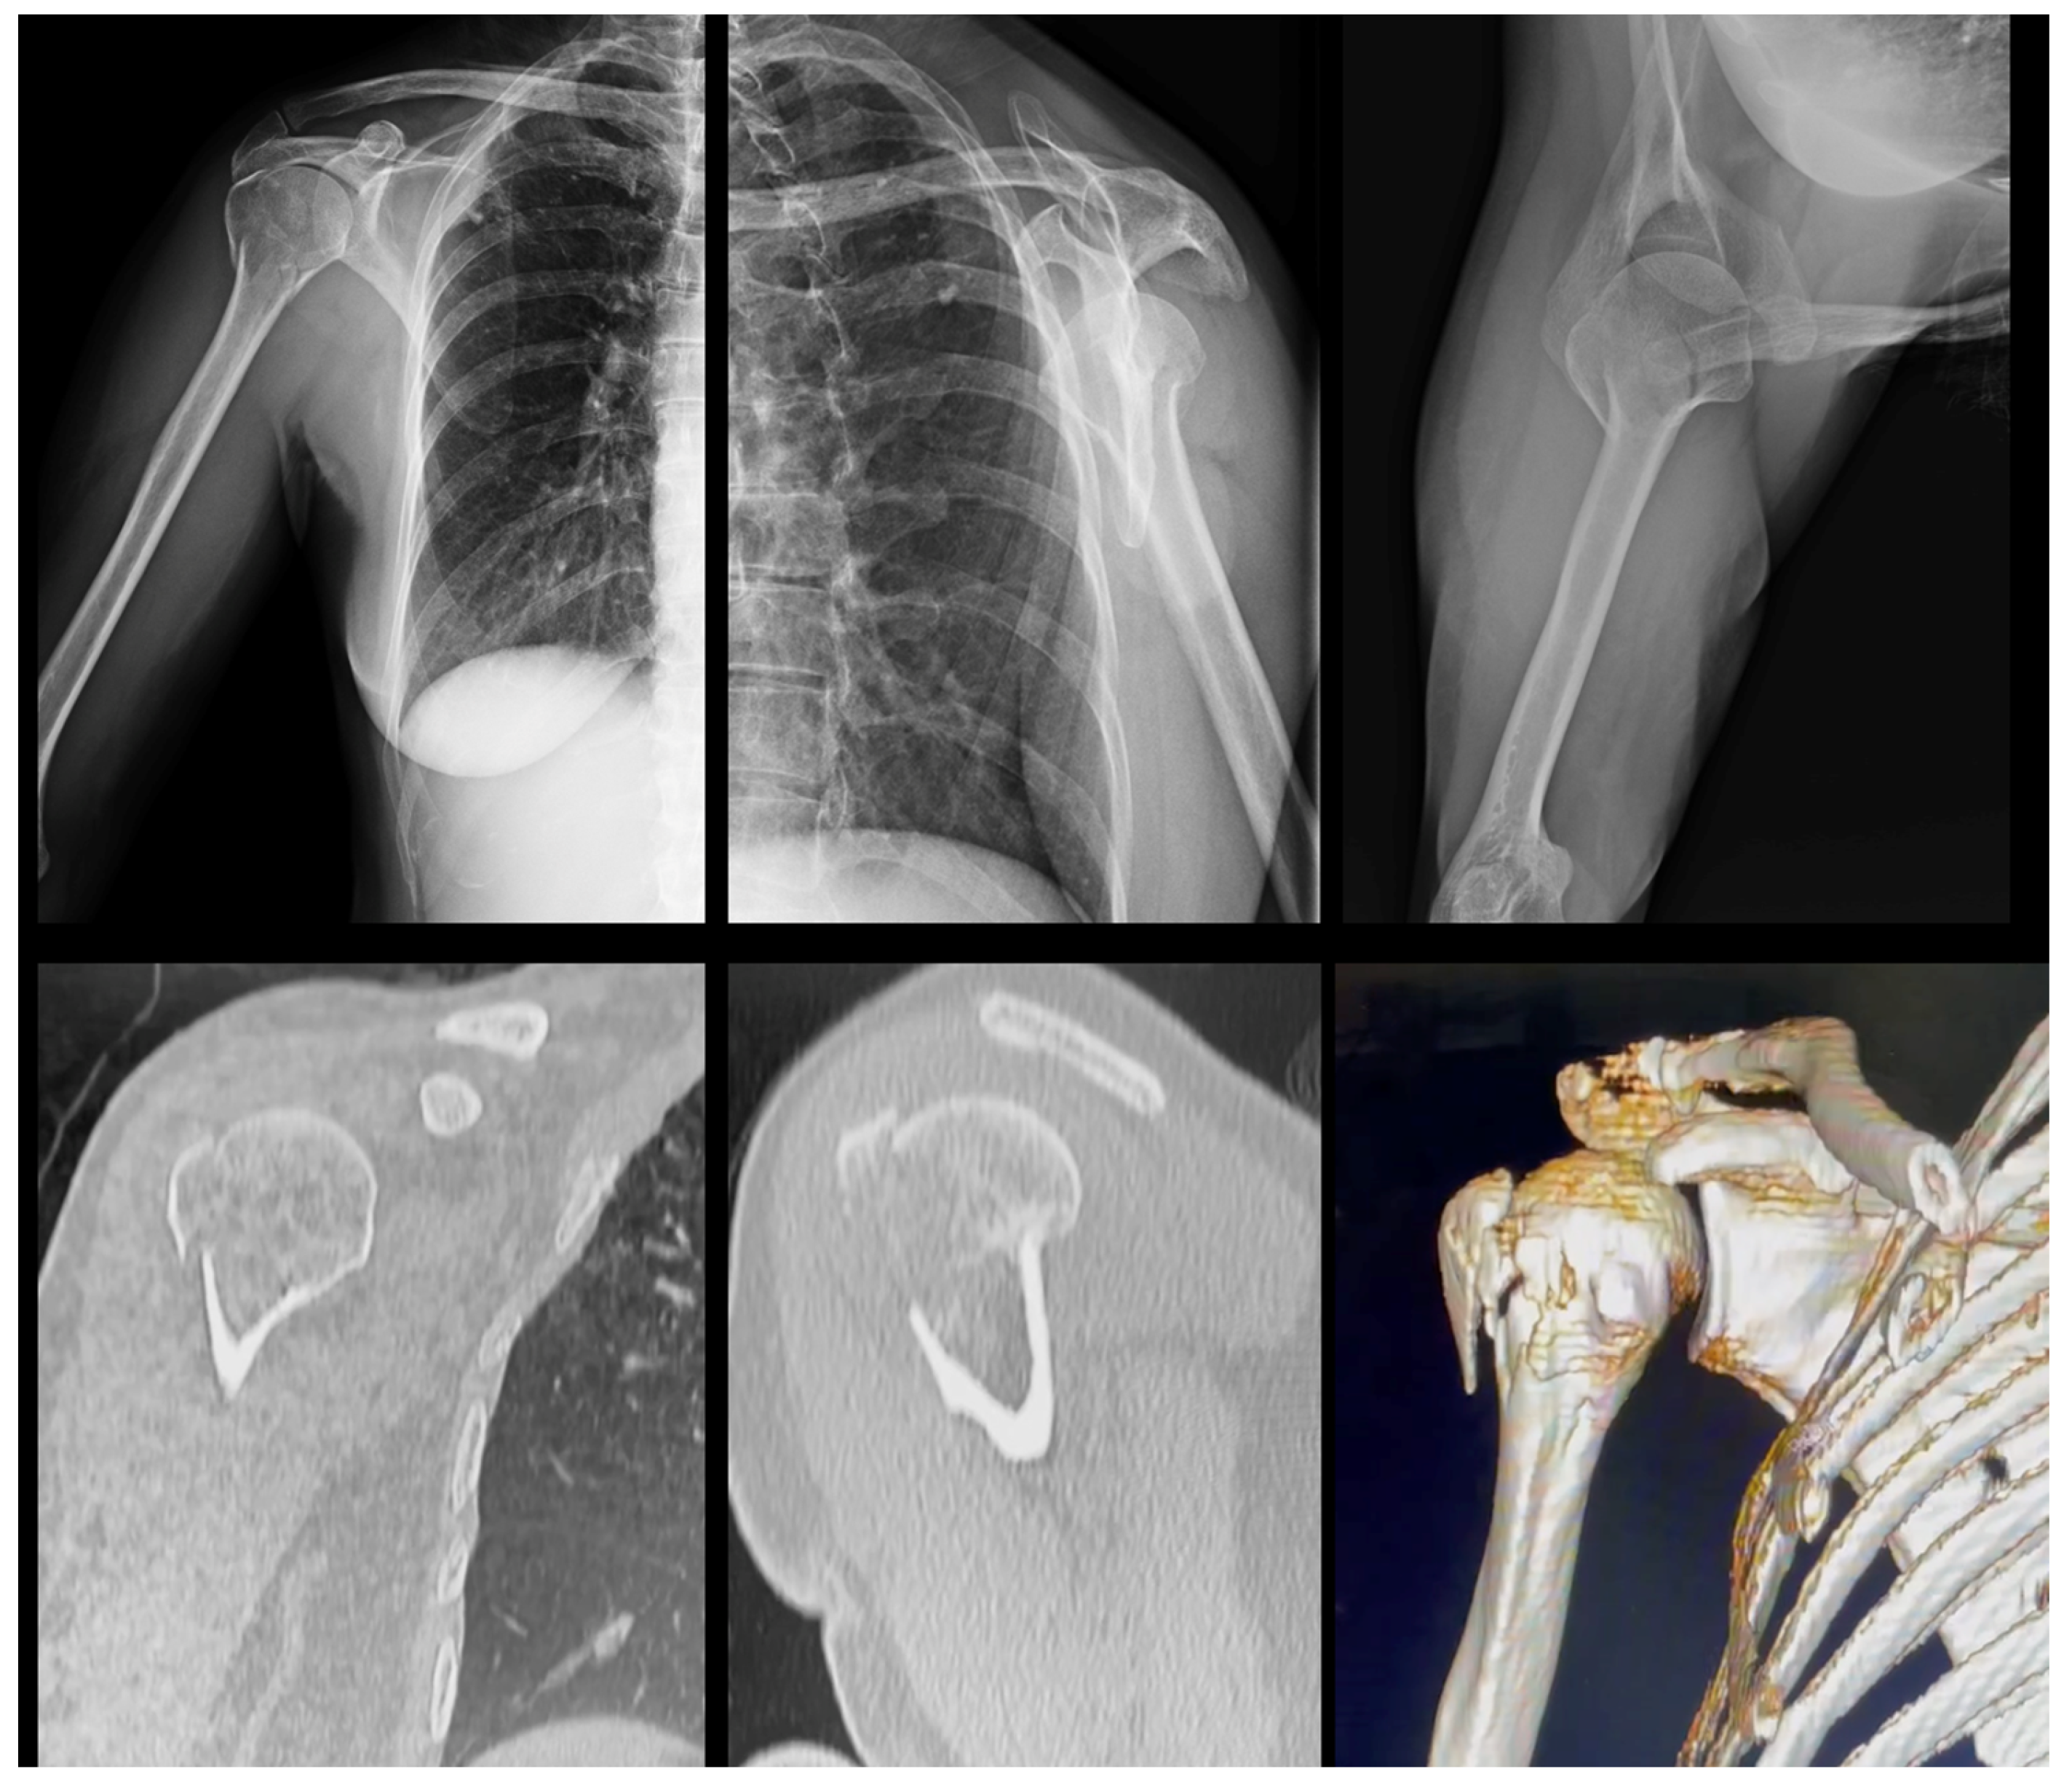

- We separated 20 cases of fractures of the proximal humerus, with X-rays and CT images, individualized in a separate folder;

- We ask that each examiner define which Hertel criteria are present by evaluating the radiographs and then their respective CT scans;

- In the folder with the files there is a photo explaining each of the 3 Hertel criteria, (reproduced from these author original article);